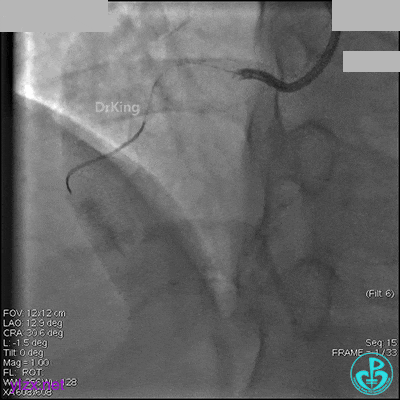

1周后再次上台,右冠脉3级血流,3段局限性严重狭窄,内膜模糊,应该是上次操作夹层遗留下的血肿。

先处理前降支开口严重狭窄并顺利植入前降支到左主干支架。